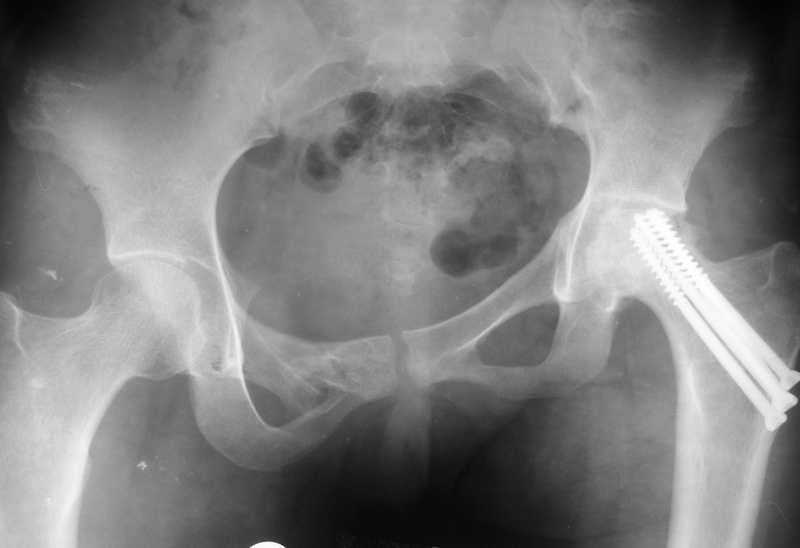

Привет всем. Укорочение за счет таза не менее 3см.

В задних отделах таза ничего не изменилось (см снимок в аппарате). Картинка кажется лучше за счет оссификата в седалищной вырезке от задней колонны к кп сочленению.

До сих пор идут большие дискуссии по поводу высокого центра ротации и единого мнения, насколько я знаю, нет. Компенсация длины, рычагов ягодичных мышц и т.д., а уж при вертикальном смещении таза,влияние его на последующее эндопротезирование просто не узнать (слишком мало наблюдений и много факторов, влияющих на конечный результат). Фото лишний раз подтверждают, укорочение за счет контрактуры.

Все-таки основное укорочение за счет таза-смещение дна вертлужной впадины вверх порядка 3 см., плюс разворот, дающий приводящую контрактуру и укорочение еще 3-4 см.

По первым снимкам имеется сложная травма с переломом ацетабулума (видна линия перелома в задней колонне) и таза с ипсилатеральным переломом шейки. Не удалось репонировать крестцово-подвздошное сочленение, и смещение с ротацией осталось, особенно в верхней ветви лонной кости. Клинические снимки подтверждают остаточную деформацию и укорочение конечности за счет таза.